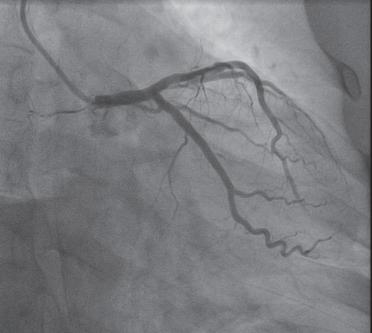

以股动脉为进针点,常规消毒铺巾,用利多卡因逐层麻醉,显效后穿刺股动脉,成功后常规置入6F股动脉鞘,沿鞘管注入肝素钠注射液3000U、硝酸甘油200μg,在X线透视下,经鞘管送入直径0.035in、长150cm的J头导丝,经股动脉、髂动脉、腹主动脉、主动脉弓到达升主动脉,再经导丝送入6F JR4造影导管行右冠状动脉造影(图1-1-3),送入6F JL4造影导管行左冠状动脉造影。造影完成后,股动脉穿刺口压迫30分钟,或用血管缝合器缝合,再予弹力绑带加压包扎,送患者安返病房。

图1-1-3 右冠状动脉造影